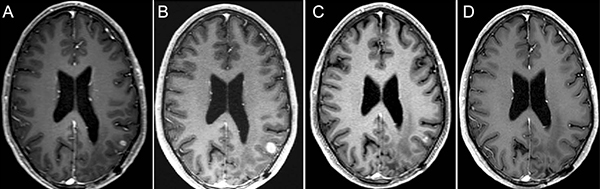

Figure 1: 36-year-old man with IDH wild-type MGMT promoter methylated GBM, treated with selinexor on Arm D, given as second-line therapy after progression of disease to radiotherapy and temozolomide.

Magnetic resonance contrast-enhanced axial T1 images taken throughout the course of treatment are shown 7 weeks before selinexor (A) at baseline 1 week before selinexor (B), and during a partial response after 16 weeks of treatment (C), and then complete (D) response beginning after 24 weeks of treatment and confirmed after of 32 weeks of treatment (not shown).